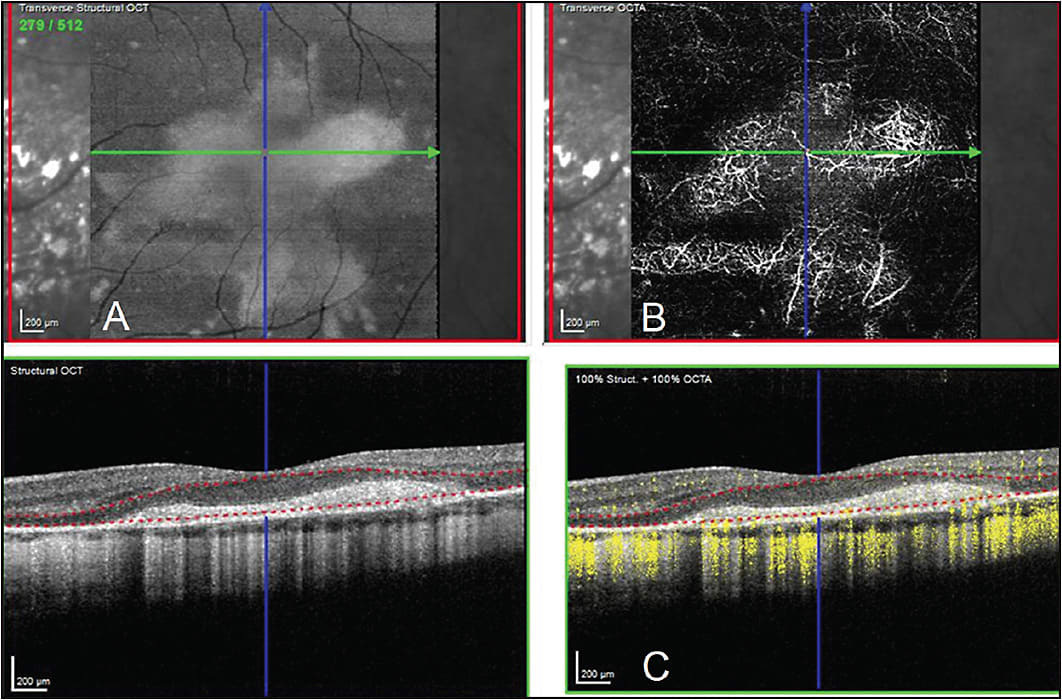

Previously, the gold standard for imaging choroidal neovascular membranes (CNVM) was fluorescein angiography (FA). OCT has allowed us to indirectly evaluate for CNVMs through the presence of fluid within or underneath the retina. The introduction of OCTA technology has allowed retina specialists to image CNVMs without the invasive and time-consuming process of FA.1 By scrolling through the OCTA volume, CNVMs can be localized in the macula both in distance from the fovea and in retinal depth.(Figure 1; Video).

Video. OCTA demonstrating a retinal angiomatous proliferation (RAP) lesion. Bottom right-hand image shows an OCT B-scan demonstrating flow (yellow) signal traversing the depth of the entire retina next to the blue line. As the segmentation selection lines (red dashed lines) go from the inner retinal layers through the outer retinal layer, the en face angiography image in the upper-right hand image shows the structure of the RAP lesion traversing the entire retina in the crosshairs of the blue and green lines. The blue line corresponds to the blue localizer line on the OCT B-scan and the green line is the location of the OCT-B-scan in the macular cube. Two other RAP lesions are noted as well in the en face angiographic images superior and inferiorly as well but outside the selected B-scan.

The 3-dimensional aspect of OCTA images helps to distinguish type 1 and type 2 CNVMs based on their presence below or above the RPE, respectively.1 This depth information can also be useful for identifying type 3 CNVMs, also known as retinal angiomatous proliferation (RAP) lesions, by scrolling through the volume cube and following the RAP lesion as it dives deeper into the outer retina and choriocapillaris (Figure 2).2